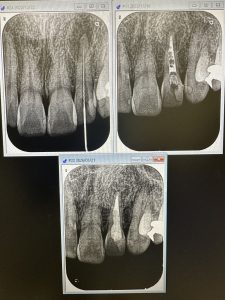

根管治療MTA.ヤグレーザー、ソケットリフトインプラント2本、ジルコニア9本

根尖から遠方より段々と骨化している

大きな病巣は5年位経過を追うと良い